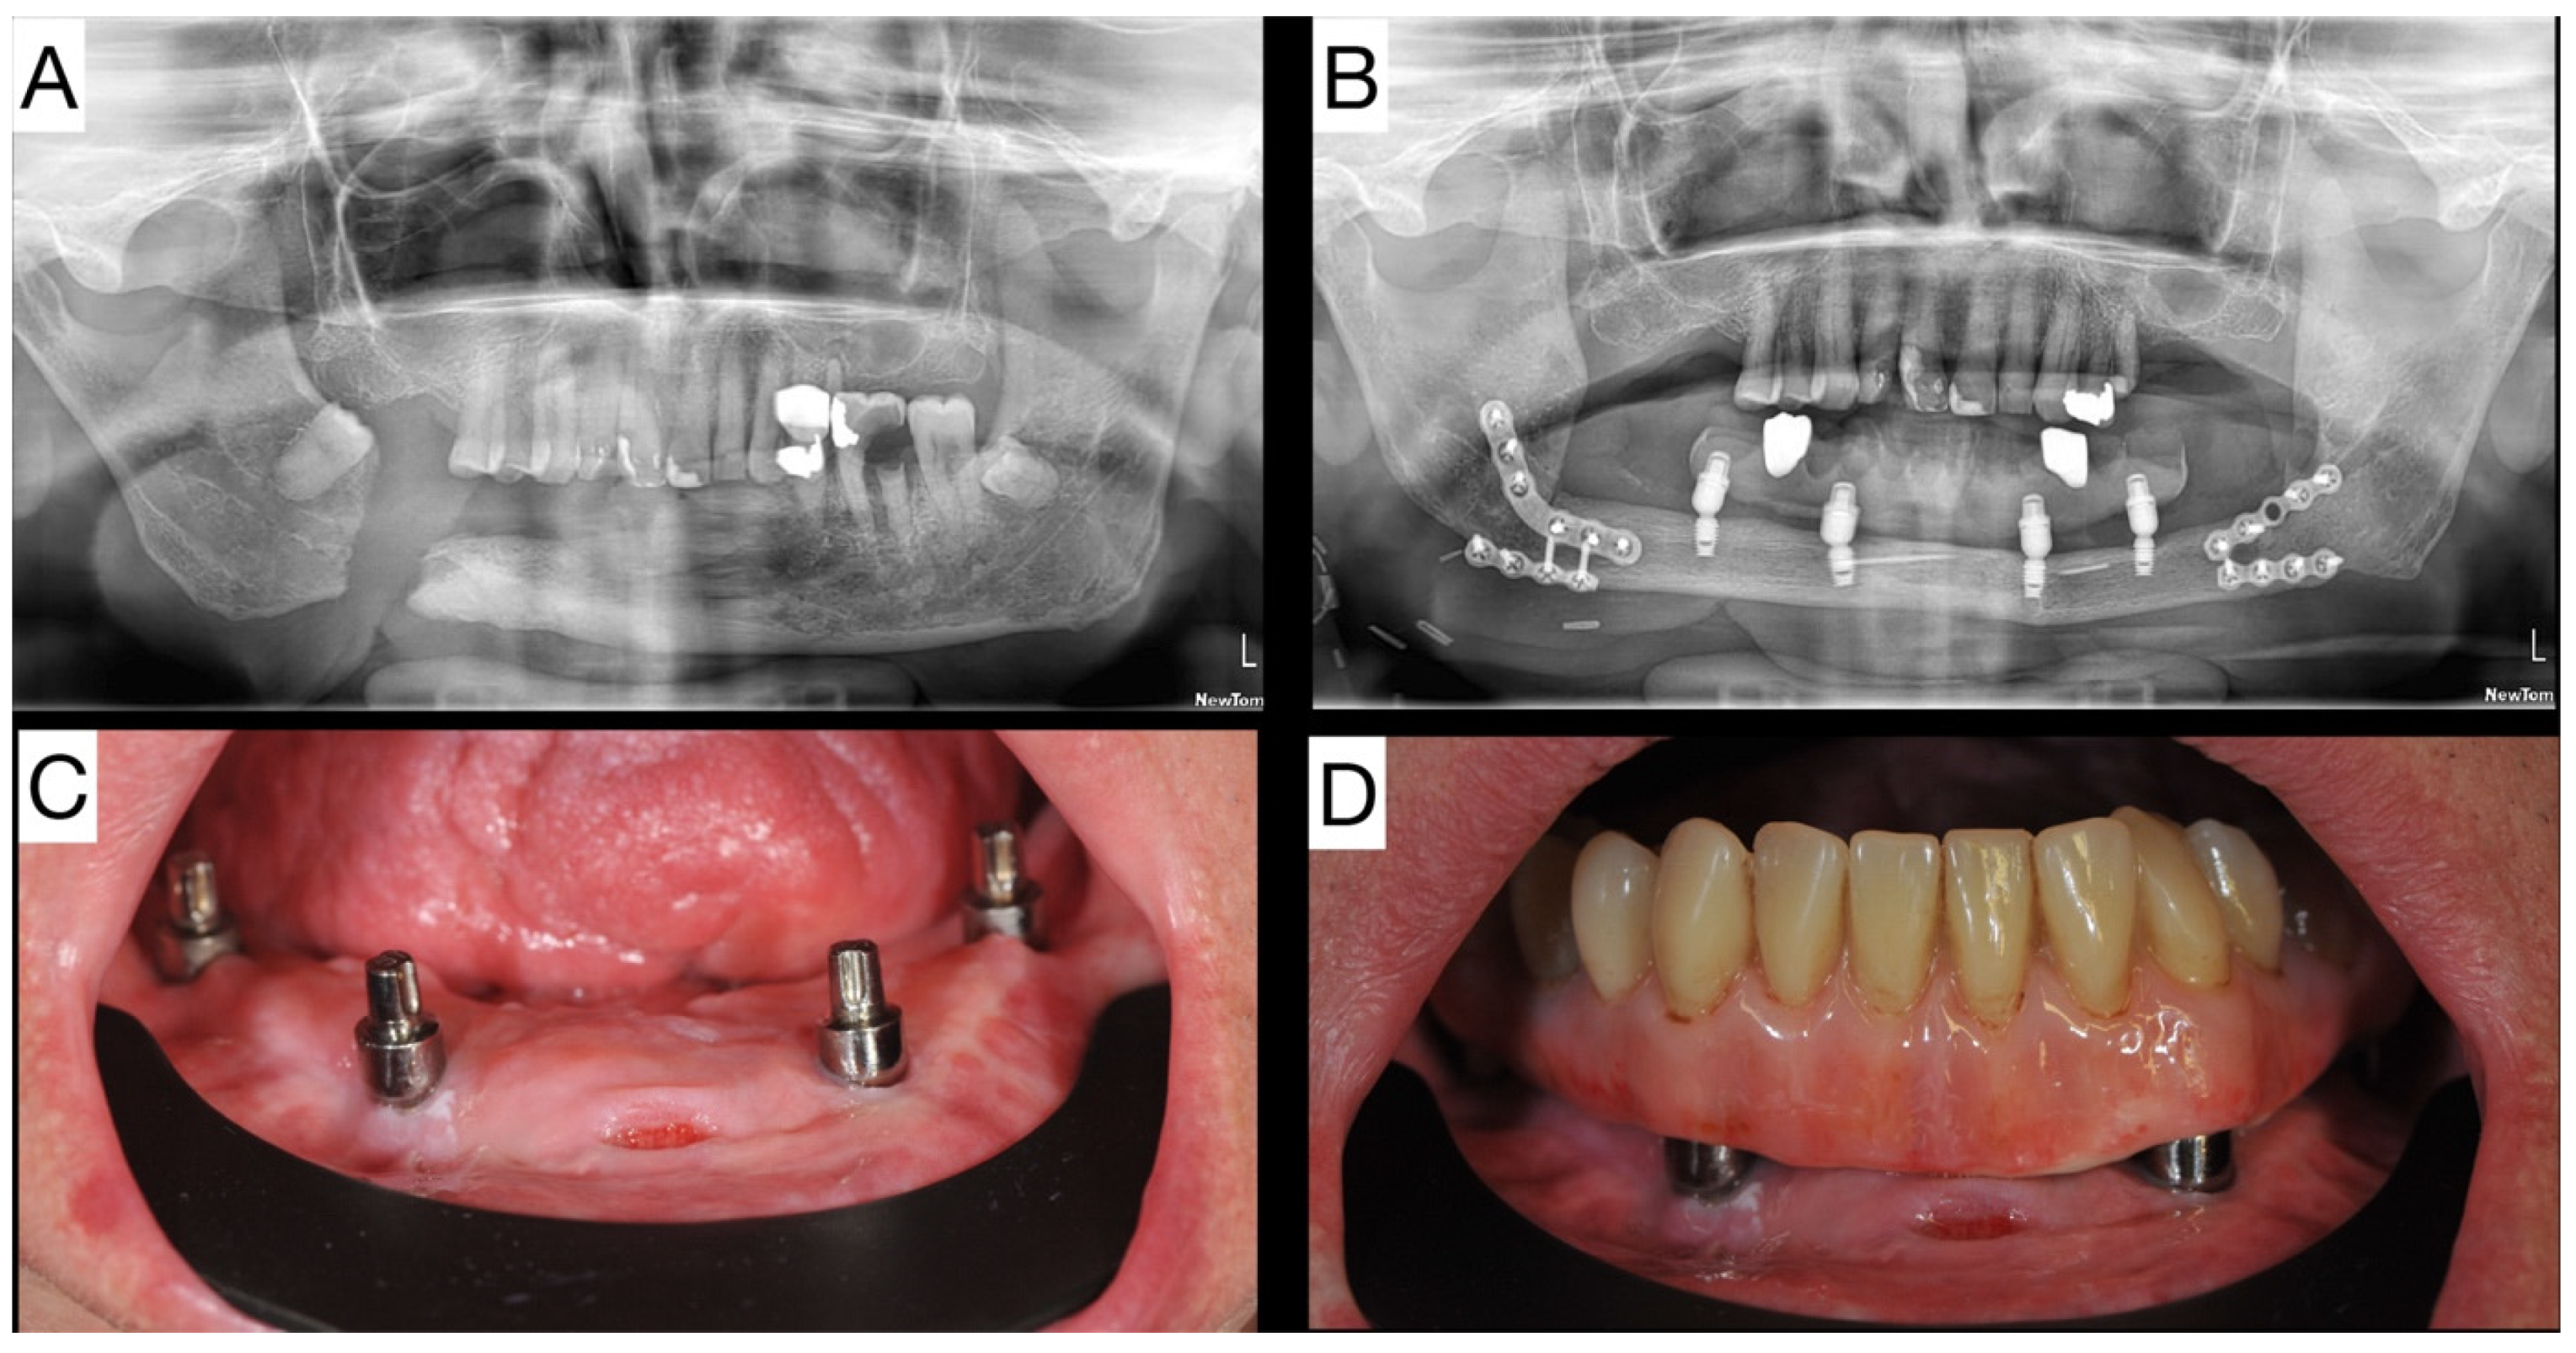

2.1. Patient 1—Case Report of Extra Short Dental Implants in Fibula Free Flap

2.2. Patient 2—Case Report of Extra Short Dental Implants in DCIA

| Patient No. 1 | Male | 67 | Mandible | FFF | 4 | 4.0 × 6.0 Integra CP | Prosthetic work in function |

| Patient No. 2 | Male | 51 | Mandible | FFF | 3 | 4.0 × 6.0 Integra CP | Adjusting prosthetic work |